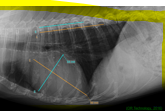

Computed radiography - What has occurred in this image to make it non-diagnostic?

Two images are seen in the image which are the Cranial caudal stifle joint, and the Medial lateral stifle joint

Computed radiography - Why might this image be non-diagnostic?

The cassette didn’t clear before taking the second x-ray